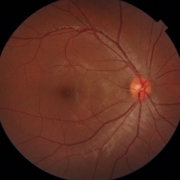

緑内障治療に精通した専門医が3名在籍し、病状や進行度に応じた最適な治療をご提案します。早期発見・早期治療を重視しています。

緑内障や黄斑疾患との併発症例など、難症例にも対応しています。